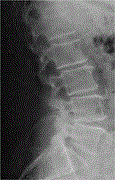

Lumbar vertebral body and pars fractures following laminectomy

Akshay Yadhati and others

Journal of Surgical Case Reports, Volume 2017, Issue 2, February 2017, rjx007, https://doi.org/10.1093/jscr/rjx007